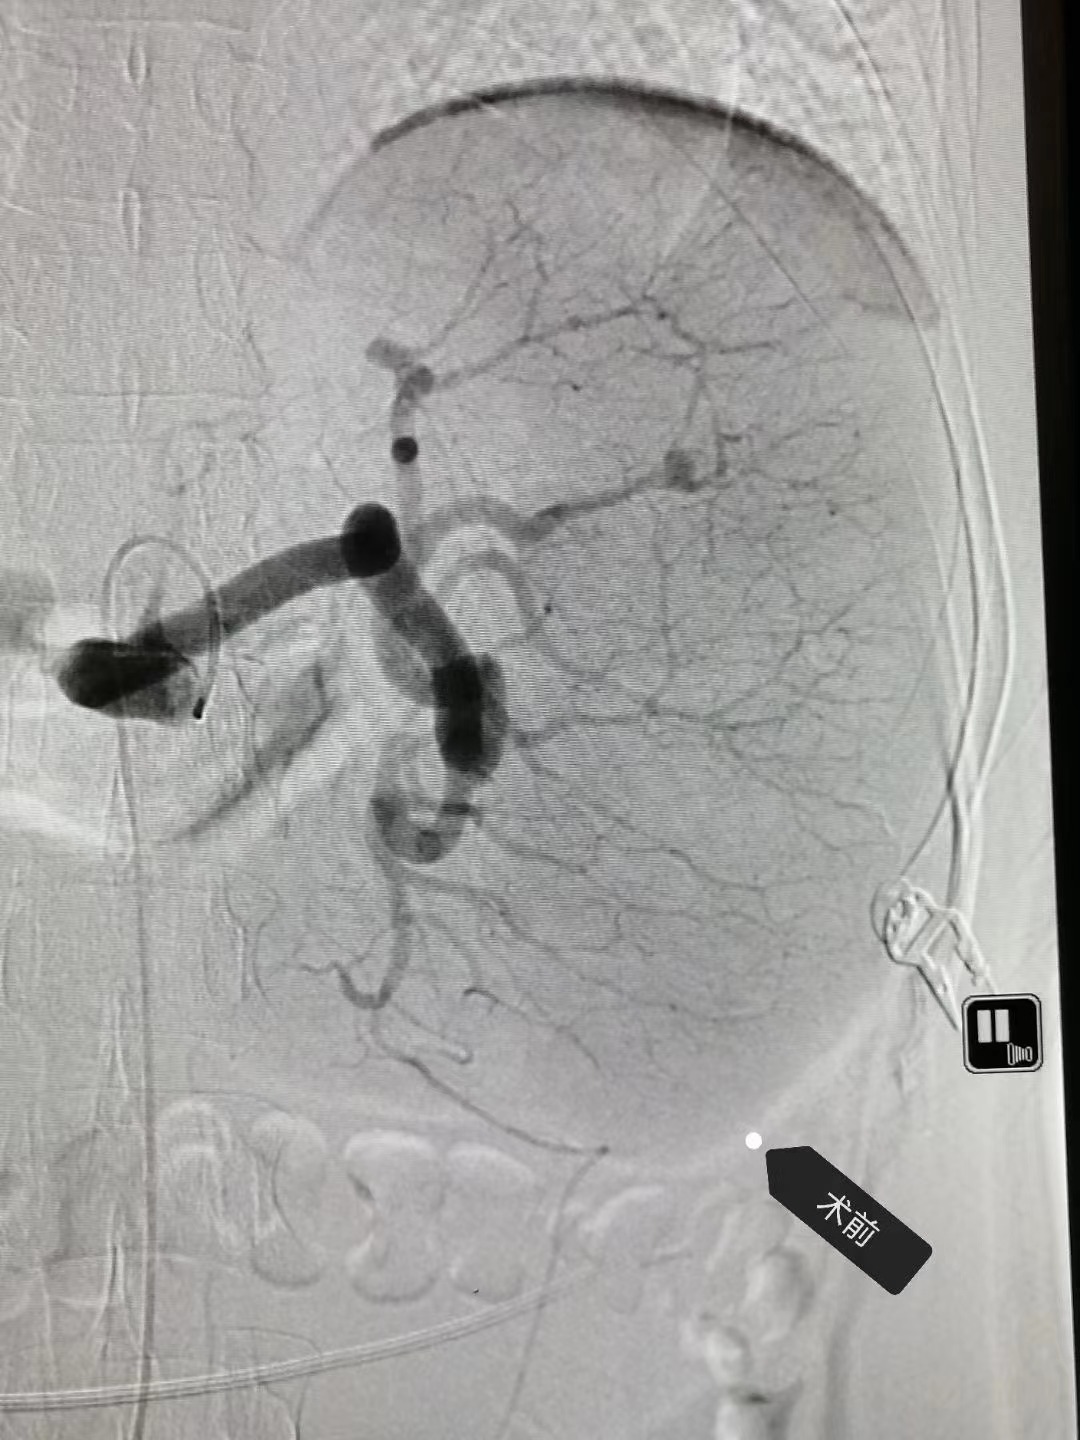

部分脾动脉栓塞术